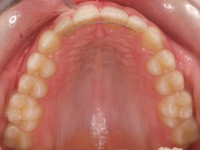

El paciente A.J. de 11 años, acude a nuestra consulta con apiñamiento maxilar importante. El canino lateral (12) está en mordida cruzada. Presenta una Clase II molar y canina, y la línea media está desviada. Se realizó un tratamiento con brackets autoligables metálicos de smartclip 022. La duración del tratamiento fue de 22 meses.

El paciente actualmente ha terminado el tratamiento con brackets y lleva una contención fija de 2-2 en maxilar y 3-3 en mandibular; para complementar también lleva una férula ESSIX durante la noche.

INICIO FINAL